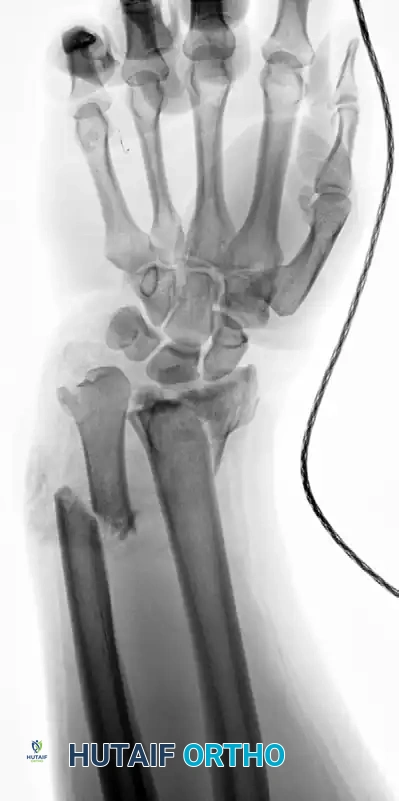

Figure 57-82A: Preoperative AP radiograph of a displaced both-bone forearm fracture in an adult.

Figure 57-82B: Preoperative lateral radiograph demonstrating significant translation and loss of the radial bow.